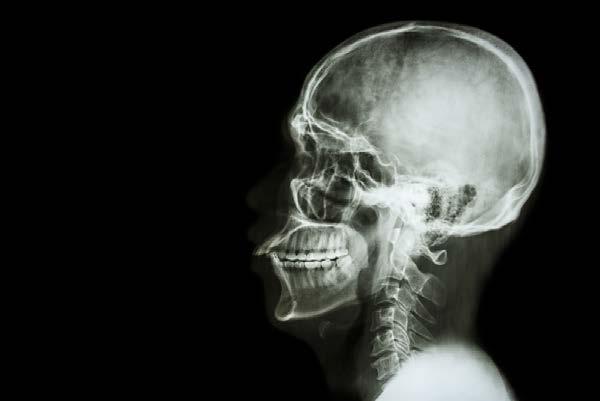

AudioLearn's Medical School Crash Courses presents Radiology

Written by experienced professors and professionally narrated for easy listening, this crash course is a valuable tool both during school and when preparing for the USMLE, or if you’re simply interested in the subject of Radiology.

The audio is focused and high-yield, covering the most important topics you might expect to learn in a typical Medical school Radiology course. Included are both capsule and detailed explanations of critical issues and topics you must know to master Radiology. The material is accurate, up to date and broken down into bite-sized sections. There are key takeaways following each chapter to drive home key points and quizzes to review commonly tested questions.